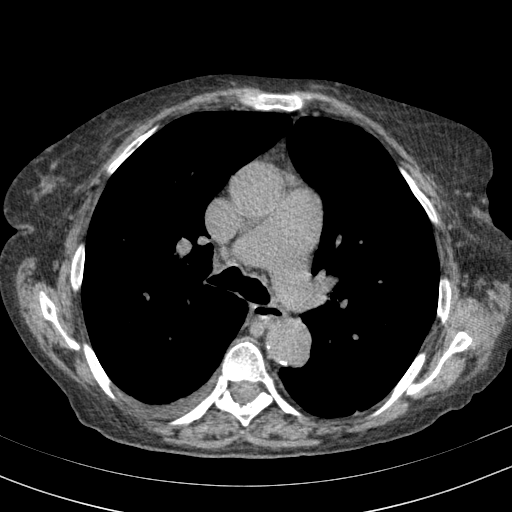

Targeted Slice 70 - Mediastinum Window Analysis (Generated vs Real Venous)

0.629

Mediastinum SSIM

49.0

Mediastinum RMSE

22.4

Mediastinum MAE

Average Mediastinum Window Metrics Across All Slices (153 slices) - Generated vs Real Venous

0.549

Mediastinum SSIM (Avg)

54.0

Mediastinum RMSE (Avg)

28.3

Mediastinum MAE (Avg)

Original VENOUS CT scan

Full window (WL 1023.5, WW 4095 β†’ Low βˆ’1024, High +3071)

Lung window (WL -600, WW 1500 β†’ Low βˆ’1350, High +150)

Mediastinum window (WL 40, WW 400 β†’ Low βˆ’160, High +240)